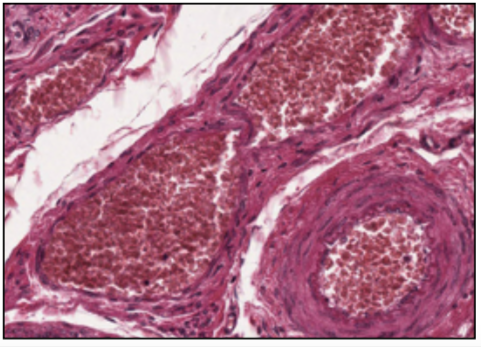

PURKINJE FIBRES (WITH PAS PROCEDURE - MAGENTA)

- large modified muscles

- large vacuoles

- few myofibrils therefore pale H&E

- stores of GLYCOGEN (PAS)

CARDIAC CONDUCTION